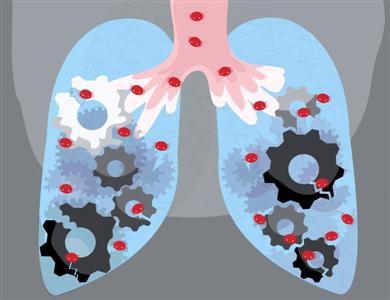

卡泊芬净和伏立康唑都是抗真菌药物,对比两种药物哪个好根据患者的病情和治疗情况而异。具体来看,卡泊芬净是一种棘白菌素类抗真菌药,它通过抑制真菌细胞壁中的β(1,3)-D-葡聚糖的合成来发挥抗真菌作用。它主要用于治疗成人和儿童患者的真菌感染,包括中性粒细胞减少、伴发热病人的可疑真菌感染以及其它治疗无效或不能耐受的侵袭性曲霉菌病等。卡泊芬净的耐受性较好,对肾功能无明显影响,且毒性相对较低。伏立康唑则是一种广谱的三唑类抗真菌药,它通过干扰真菌的细胞膜合成来达到抗真菌的效果。伏立康唑主要用于治疗侵袭性曲霉病,对氟康唑耐药的念珠菌引起的严重侵袭性感染,以及由足放线病菌属和镰刀菌属引起的严重感染。

首先,从药物分类和机制来看,卡泊芬净是一种半合成脂肽(棘白菌素)化合物,它通过抑制真菌细胞壁中的β(1,3)-D-葡聚糖的合成来发挥抗真菌作用。而伏立康唑片则是一种三唑类衍生物,它通过抑制麦角甾醇的生物合成来达到抗真菌的效果。

其次,从适应症上来看,卡泊芬净主要用于治疗成人和儿童患者的真菌感染,包括中性粒细胞减少、伴发热的可疑真菌感染,以及对其他治疗无效或不能耐受的侵袭性曲霉菌病等。而伏立康唑片则主要用于治疗侵袭性曲霉病、对氟康唑耐药的念珠菌引起的严重感染,以及由足放线病菌属和镰刀菌属引起的严重感染等。